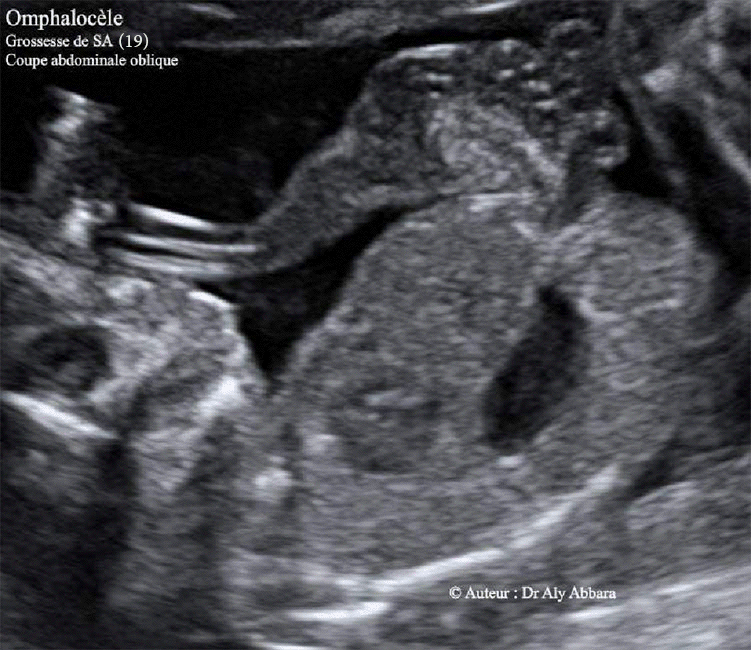

- Images échographiques montrant une grossesse de 19 SA caractérisée par la présence d'une volumineuse omphalocèle contenant une partie des anses grêles et une composante kystique uniloculaire.

Les autres anomalies fœtales associées à cette omphalocèle : un canal atrio-ventriculaire et une bradycardie constante à 80 - 60 bpm ; une fente labiale unilatérale, et enfin, un retard de croissance sévère et harmonieux.

Le caryotype fœtal ne montre pas d'anomalie chromosomique associée (46, XX).